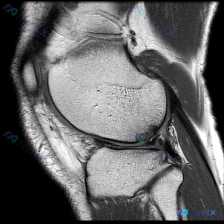

看到这个很有代表性的读片病例,整理出来和大家分享,这个临床-影像不匹配的情况其实临床工作中挺常见的。 病例基本信息 本次分析基于一张膝关节矢状位T1加权磁共振图像,临床提示存在「chondral abnormality(软骨异常)」,无其他病史、体征或检验结果提供。 影像基本观察(单张T1序列) 先...

看到一个有意思的影像读片问题,整理了完整的分析思路分享给大家。 病例/影像基本信息 这是一张单幅膝关节矢状位T1加权MRI影像,问题是观察图像中是否存在软骨异常。 影像本身特点:图像有明显噪声(颗粒感重),对比度一般,解剖结构轮廓可辨认,但精细细节分辨率受限,属于质量不佳的单幅影像。 系统性影像观察...

整理了一份很有参考意义的影像读片病例,核心问题是:这张膝关节MRI-T1序列矢状位图像上,能观察到软骨异常吗?把整个分析思路分享给大家。 一、影像基础信息 这是一幅标准的膝关节矢状位T1加权像,图像对比度良好,骨髓腔呈正常高信号(脂肪髓),皮质骨呈低信号,解剖结构显示清晰,无明显运动或金属伪影;图像...

遇到一个挺典型的读片问题,整理出来和大家分享一下思路: 病例背景 临床关注点:怀疑膝关节软骨异常,提供单张膝关节MRI矢状位T1加权像(T1WI)读片 影像基础评估结果 先把影像上能看到的情况理清楚: 1. 骨性结构:股骨远端、胫骨近端皮质连续,没有骨折;骨髓信号是正常脂肪骨髓的灰白色信号,没有局灶...

刚整理了一份有意思的膝关节MRI读片病例,临床提示观察到软骨异常,但单张T1加权矢状位影像却没看到明确异常,把分析思路整理出来和大家讨论。 一、病例基本影像信息 这是一张膝关节T1加权矢状位旁矢状位MRI图像,显示区域包括股骨远端、胫骨近端、髌骨、髌腱、Hoffa's脂肪垫和部分后交叉韧带,主要观察...

今天遇到一个有意思的读片问题:临床怀疑膝关节软骨异常,但提供的单张矢状位T1加权MRI读下来基本正常,整理一下分析思路和大家分享。 一、现有病例影像资料整理 这是一张膝关节矢状位T1加权MRI,图像质量清晰,信噪比良好,可见层面包含股骨远端外侧髁、胫骨近端、后交叉韧带、半月板前后角、髌韧带及Hoff...